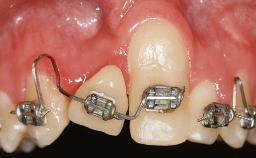

A 30-year-old woman was referred by her general dentist for evaluation of an esthetic complication related to previous implant treatment for congenitally missing maxillary lateral incisors. The patient’s chief complaint was the inadequate esthetic appearance of her smile. The case demonstrates the use of a combined approach to achieve optimal results. Two different flap designs - a tunnel technique and a coronally advanced flap - are employed based on the surgical objectives for the affected site.

Soft Tissue Grafting Yes